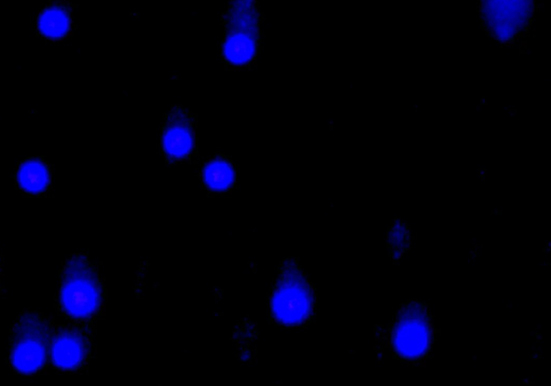

• 染色与观察:电泳结束后,用荧光染料对 DNA 进行染色,在荧光显微镜下观察并拍照,分析彗星的形态和测量相关参数,如尾长、尾矩等,以评估 DNA 损伤程度。

• 细胞在正常情况下,DNA 与组蛋白等结合形成紧密的核小体结构,DNA 链较为完整。当细胞受到如氧化应激、辐射、化学物质等损伤时,DNA 链会发生断裂,形成大小不一的片段。在碱性条件下,DNA 双链解旋,断裂的 DNA 片段会从核中释放出来,在电场作用下向阳极迁移。由于这些片段的迁移距离与 DNA 损伤程度相关,因此通过观察细胞在电泳后的形态,就像彗星一样有头部(未损伤的 DNA 部分)和尾部(断裂的 DNA 片段),从而可以对细胞的 DNA 损伤程度进行定性和定量分析。